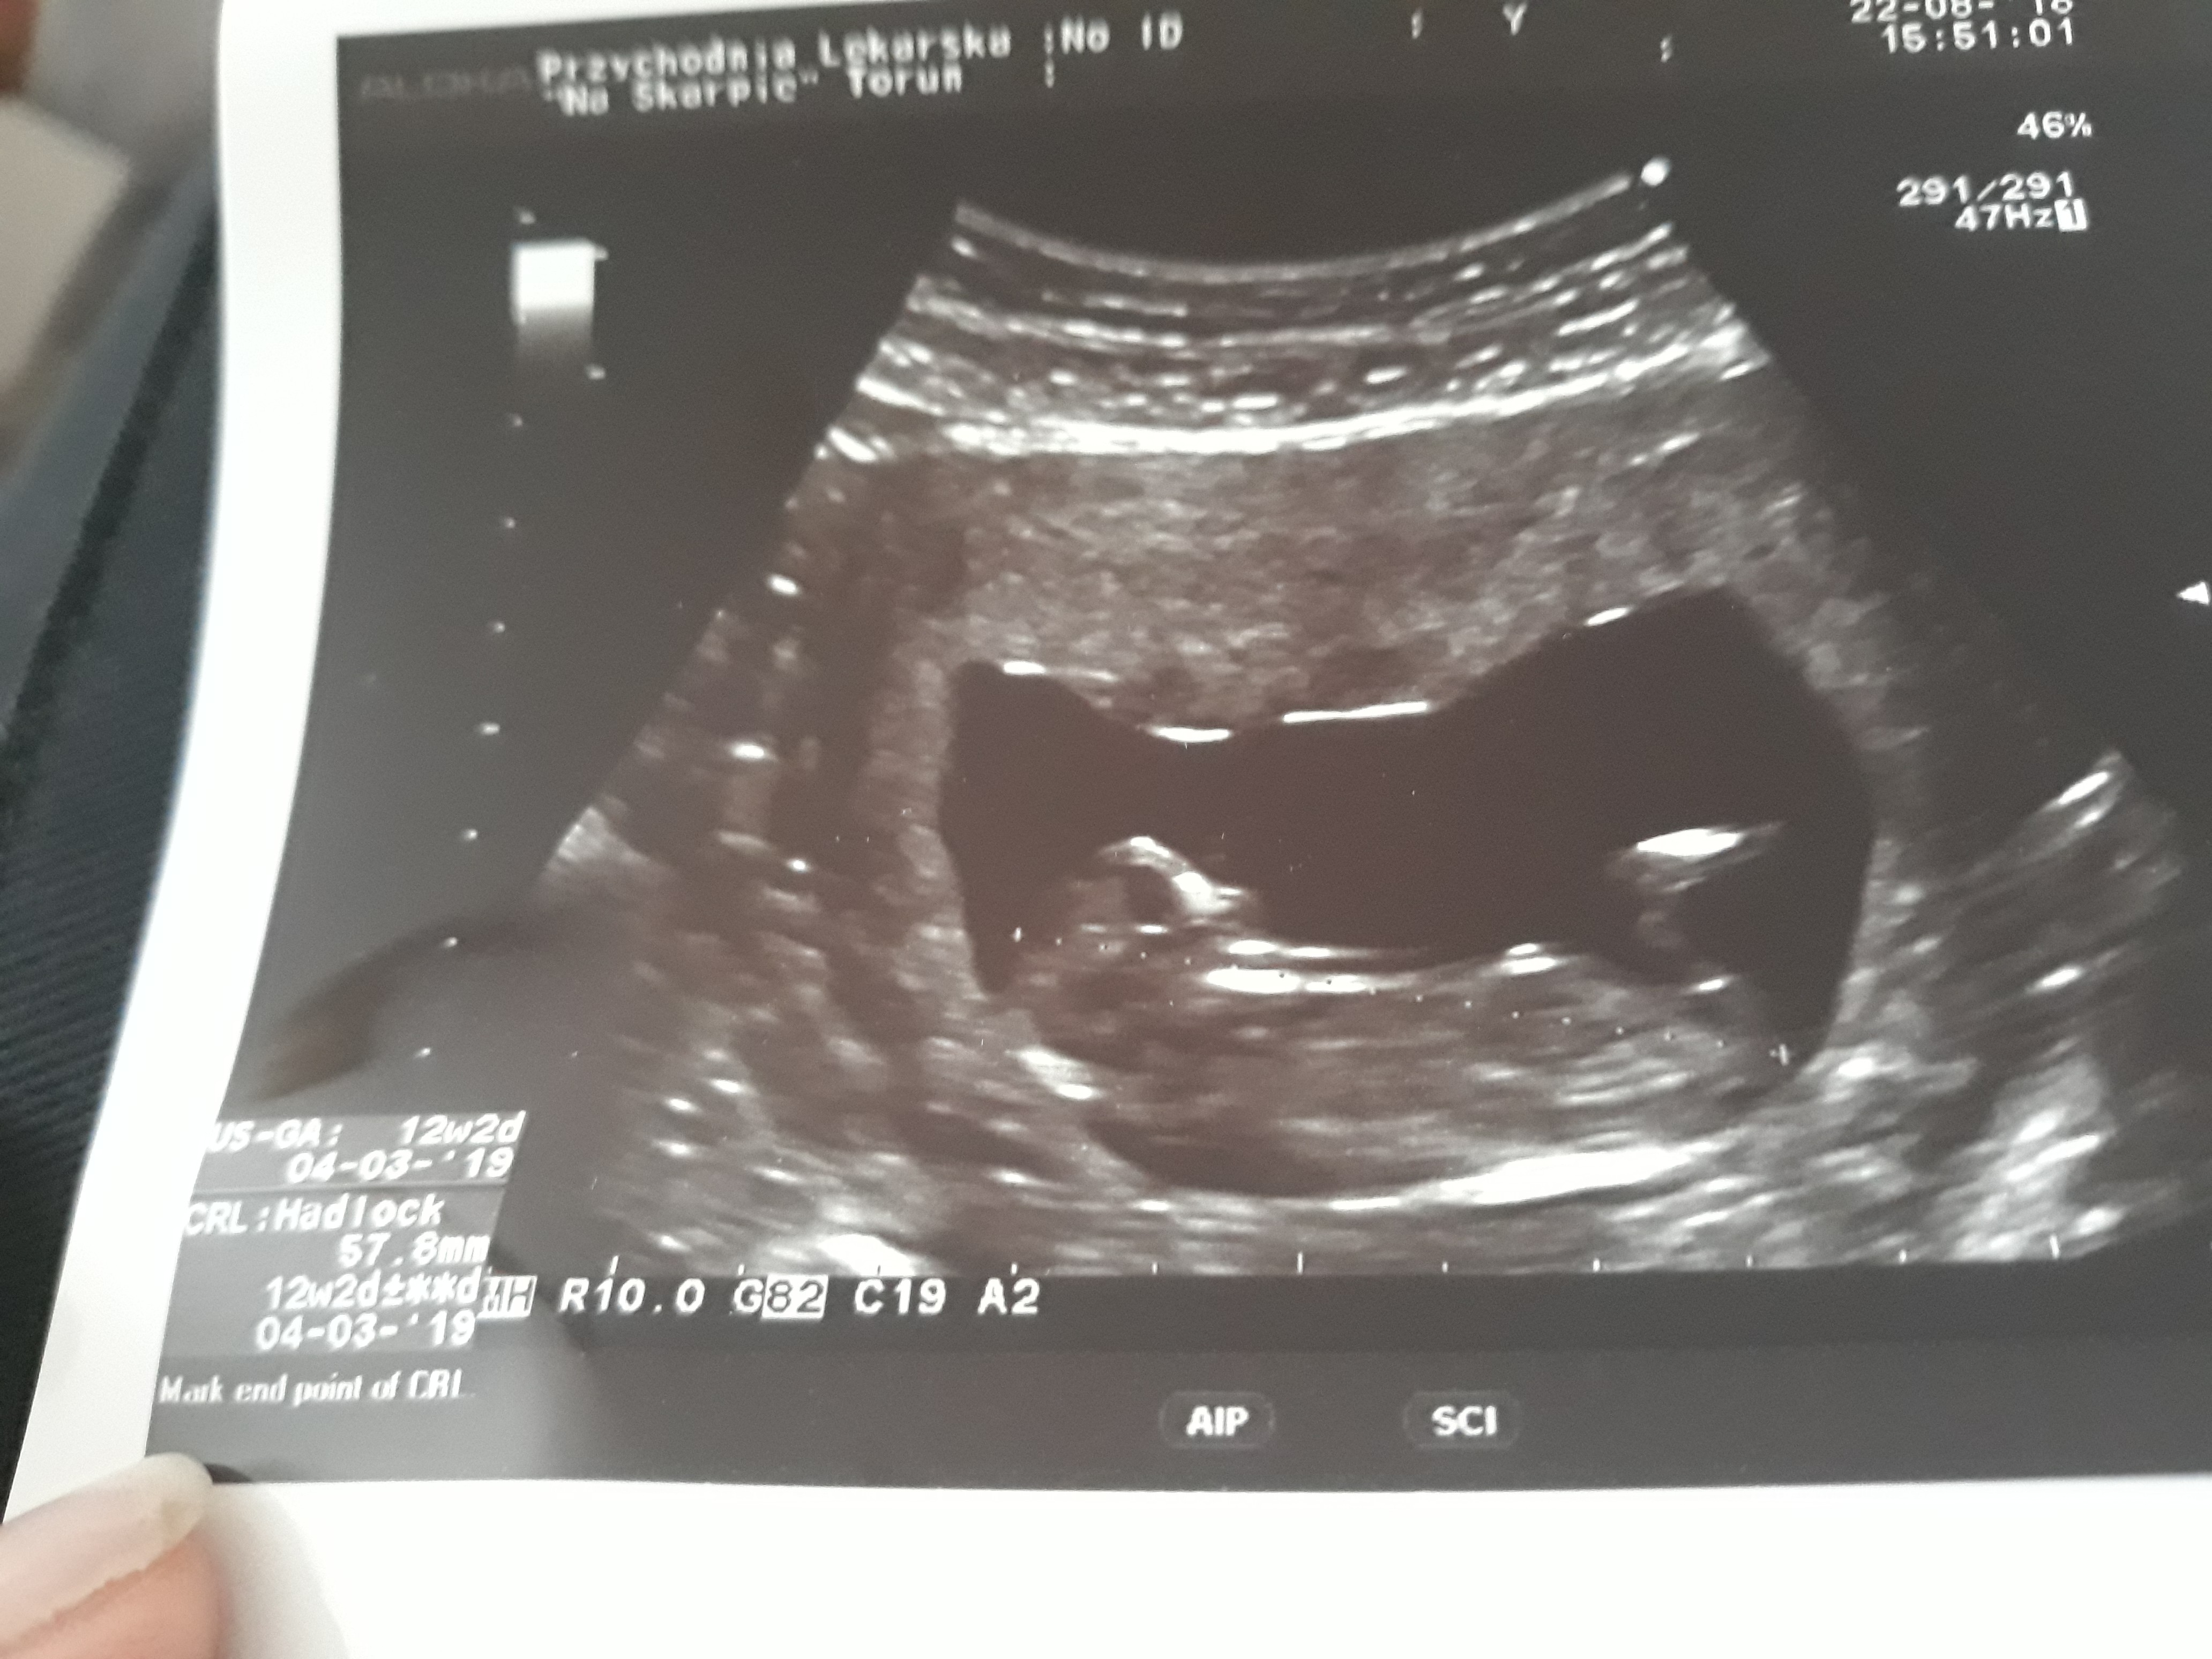

Dziecko ma 5.78 cm , przyziernosc karkowa 1.3 jeśli chodzi o serduszko powiedział tylko że bije. Mam też zdj ale bardzo słabej jakości Zobacz załącznik 890758 Zobacz załącznik 890759 Zobacz załącznik 890760 Zobacz załącznik 890760